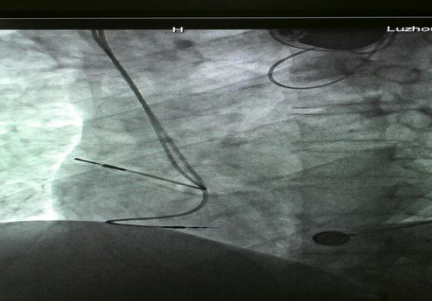

已安裝好的磁共振兼容起搏電極

近年來,隨著醫(yī)學(xué)科技的進(jìn)步帶動了起搏器的一次次革新,磁共振檢查“大門”已經(jīng)向起搏器患者開放,可以說全面“解禁”磁共振檢查的時代到來了。通過對材料和工藝在內(nèi)的一系列技術(shù)改進(jìn),有了可以兼容的磁共振起搏系統(tǒng),包括磁共振兼容脈沖發(fā)生器和磁共振兼容起搏電極。

?“磁共振兼容起搏系統(tǒng)適用于所有起搏器植入術(shù)患者。雖然現(xiàn)在磁共振兼容性起搏器已經(jīng)用于臨床,但是由于整套系統(tǒng)的昂貴價格及醫(yī)保支付等原因,一部分患者因?yàn)榻?jīng)濟(jì)原因暫時不能植入磁共振兼容全套系統(tǒng)?!敝毂蜥t(yī)師表示,心臟起搏器系統(tǒng)包含脈沖發(fā)生器和起搏電極兩部分,起搏電極的拔除和更換手術(shù)較復(fù)雜并且具有一定的風(fēng)險,而單純的脈沖發(fā)生器更換術(shù)則比較簡單。因此,對暫時不能植入磁共振兼容全套系統(tǒng)的患者,可以先植入磁共振兼容起搏電極導(dǎo)線,等到將來各方面條件成熟或需要做磁共振檢查時再直接更換脈沖發(fā)生器。此種方案可以滿足未來患者接受磁共振檢查的潛在需求。